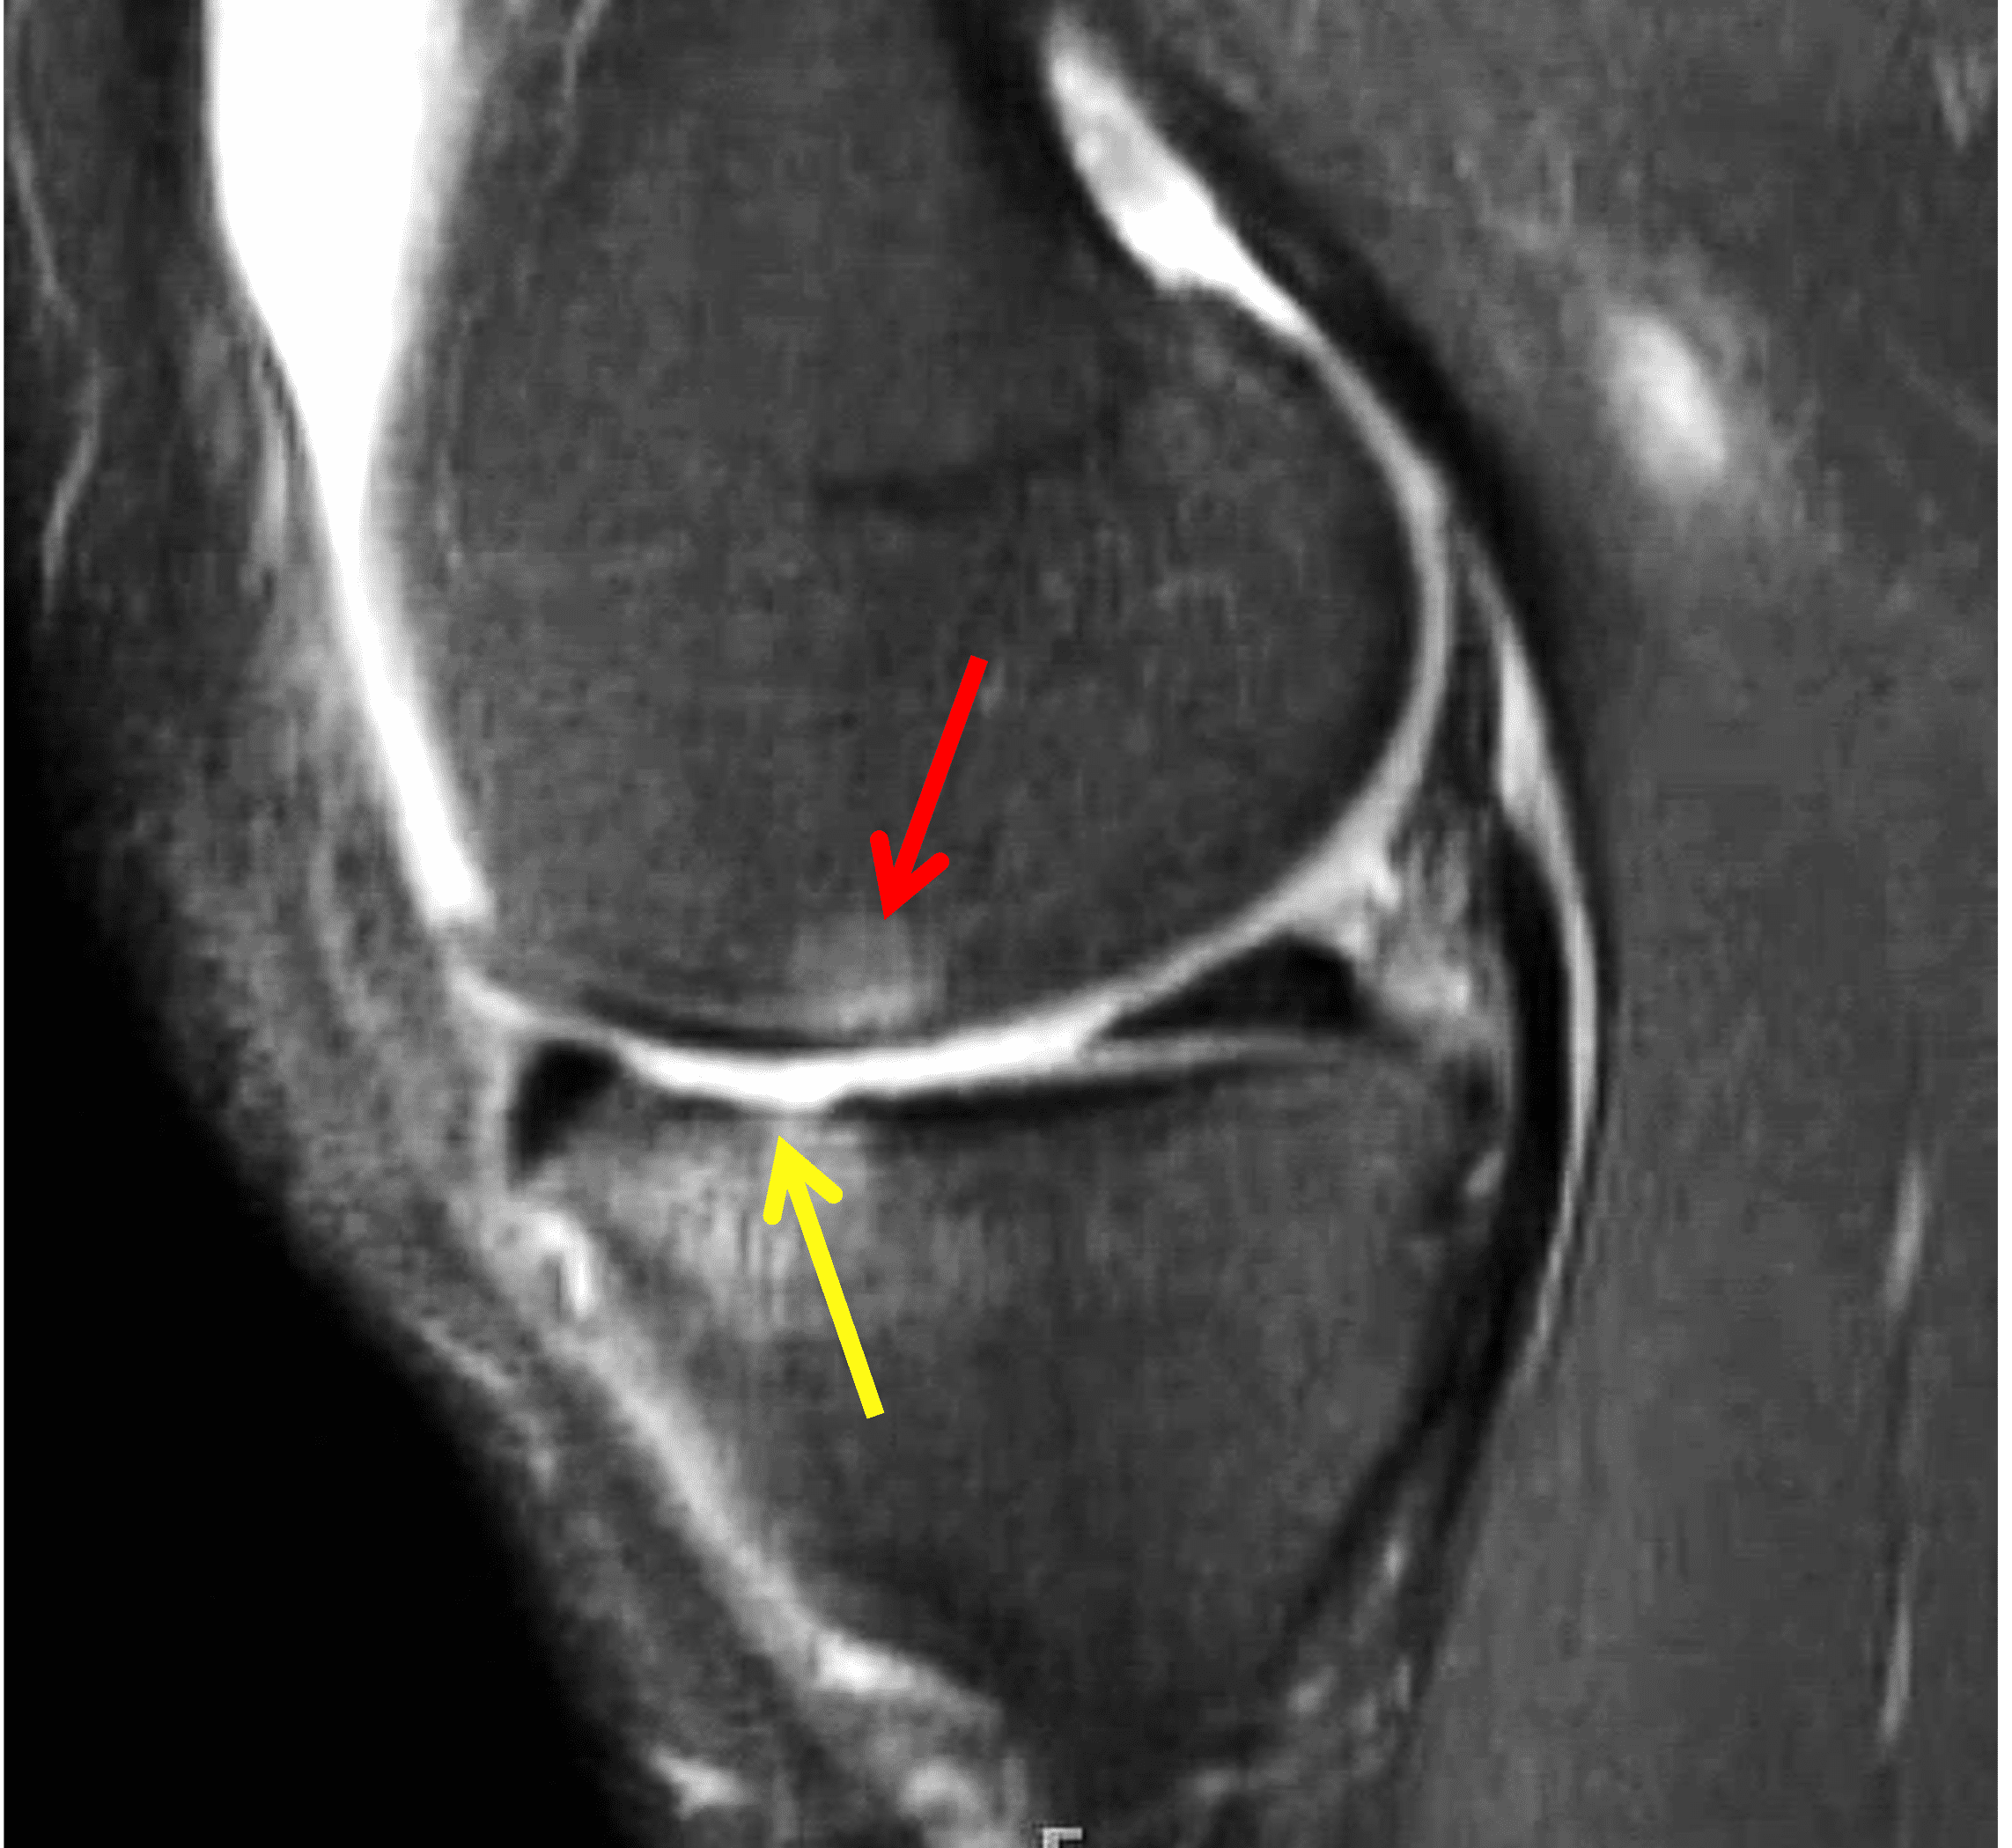

A 32-year-old man suffered a traumatic chondral injury to the medial femoral condyle that was treated with an osteochondral allograft 20 months previously. Representative images from a current knee MRI include (1A) coronal fat-suppressed fluid-sensitive and sagittal (1B) T1-weighted, (1C) proton density-weighted, and (1D) T2-weighted sequences. Are the post-operative MRI findings normal and expected, or abnormal and pathologic? Based on these images, would you characterize the procedure as a success or failure?

Figure 2: (2A) On the coronal image, the margins of the osteochondral graft are faintly visible (arrowheads). Both the graft and underlying bone show mild marrow edema, an expected finding. (2B) The T1-weighted image shows continuity of the marrow in the graft (asterisks) with the underlying bone, indicating osseous integration. A bioabsorbable pin (arrow) used for graft fixation is partly visible. (2C) The proton density-weighted image shows a low signal intensity seam (black arrow) between the native cartilage and transplant, as well as a defect in the subchondral bone plate of the graft (red arrow) where the pin was drilled, both normal findings. (2D) The T2-weighted image shows a smooth, congruent articular surface (arrows), restoring the normal anatomy, and a tiny subchondral cyst. No findings are present to suggest graft failure. The patient’s current symptoms were attributed to pathology elsewhere in the joint (not shown).